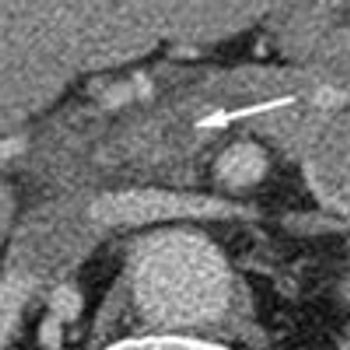

An obese 61-year-old man with a history of heroin abuse was brought to the hospital after he had fallen onto his buttocks on a sidewalk. He was able to stand initially, but weakness and numb-ness in his legs rendered him suddenly unable to walk or prevent himself from voiding. He denied abdominal or back pain. His medical history included asthma, chronic obstructive pulmonary disease, and hypertension.